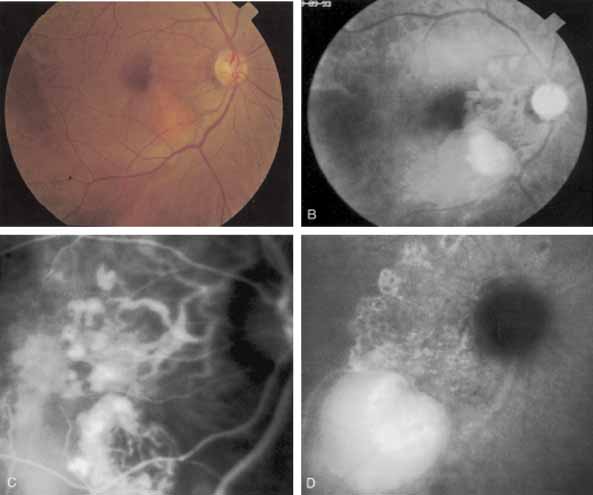

An important report by Chang and co-workers27 lends support to the rationale for interpreting the hyperfluorescence seen on ICG angiography as CNV. In this clinicopathologic study, a patient was identified who had experienced subretinal hemorrhage with early signs of occult CNV on fluorescein angiography (Fig. 4A). Fluorescein angiography demonstrated blocked fluorescence (Fig. 4B). The ICG study, however, demonstrated late staining in a well-circumscribed fashion, which the authors interpreted as a “plaque” of occult CNV (Fig. 4C). When the patient died, this area was evaluated and studied histopathologically and compared with the picture seen on ICG angiography. The area of hyperfluorescence on the ICG study corresponded precisely to a thin layer of fibrovascular tissue beneath the pigment epithelium and neurosensory retina, confirming that the late-staining tissue imaged with ICG angiography was truly a neovascular membrane (Fig. 4D).